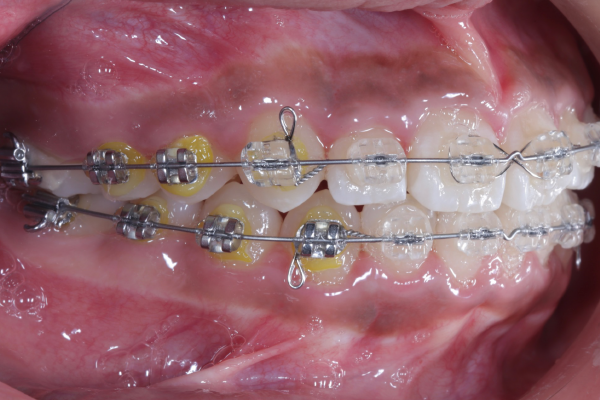

AFTER

【矯正治療開始11ヶ月】

11ヶ月経ち歯のガタガタが改善し、歯並びが綺麗になってきています。